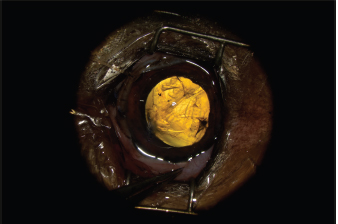

Fig. 2. Appearance of the eye after claw excision, corneal reconstruction, and pharmacological mydriasis. The tear of the anterior capsule is large and complex. The architecture of the lens is turned upside down.

The AC was stabilized by intracameral injection of a viscoelastic gel (hyaluronic acid 1.6%, Ophteis Bio) by a perforating keratotomy port at 12 o’clock. As the base of the claw was crenelated, it was not possible to remove it through the site of penetration, which is why another perforating keratotomy port was made at 10 o’clock. The claw was grasped with Bonn’s pliers and then gently removed. The entry point of the claw and the 10 o’clock port were sutured by single stitches using polyglactin 9/0 (Vicryl 9/0). The pupil was then dilated by injection of 1 ml of epinephrine at a concentration of 1 mg/ml into the AC. The anterior lens was ruptured, and a heterogeneous traumatic cataract had already developed (Fig. 2). The lens was, therefore, removed by phacoemulsification via the port at 12 o’clock. After removal of the masses by irrigation/aspiration, the tear of the anterior capsule was shaped before injection of an implant (PFI 4X, Medicontur). The keratotomy port at 12 o’clock was sutured by three single stitches with Vicryl 9/0 after the removal of residual viscoelastic material by suction irrigation. At this stage of the surgery, a tear of the endothelium and Descemet membrane was visible, following the most likely trajectory of the claw into the AC (Fig. 3). Water bubbles were already forming in the corneal stroma. An injection of 0.25 μg of tissue plasminogen activator (Actilyse®, BOEHRINGER INGELHEIM) was performed in the AC at the end of the intervention to limit postoperative fibrinous collection. The claw was sent to the laboratory for bacteriological analysis.